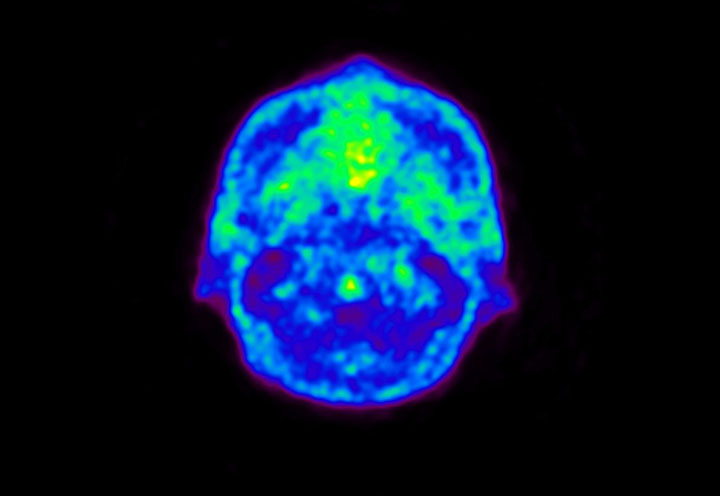

Head / Case5 : Amyloid

Courtesy : Kindai University Hospital

- Imaging protocol

- Injected dose: 4.27 MBq/kg, 18F-Flutemetamol

- Uptake time: 99 minutes

- Scan time: 20 minutes